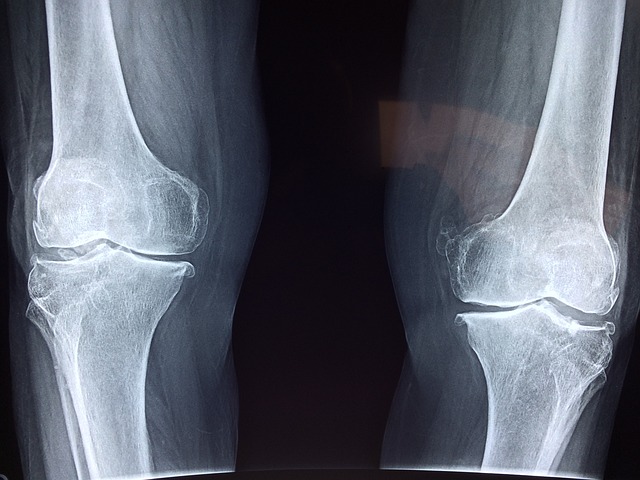

관절염이란?

1. 정의

관절이란 뼈와 뼈가 만나는 부위입니다. 관절은 뼈 사이가 부드럽게 운동하도록 연골이나 인대 등의 구성으로 조직되어있고 움직임이나 충격에 따라 그것을 흡수하는 아주 중요한 역할을 합니다.

이러한 관절에 염증이 생긴 것을 관절염이라고 합니다.

2. 증상

관절염의 증상에는 굉장히 여러 가지가 존재합니다. 아무래도 연골이 있다 보니 나이가 들면 자연스레 약해지기 마련이죠. 그러나 폭발적인 운동을 하는 운동선수나 교통사고 등의 외부 충격이 크게 다가온 사람에게는 관절의 건강이 약해져 있을 수 있죠. 나이에 상관없이 이러한 증상이 있다면 병원에 내원하시는 것을 추천드립니다.